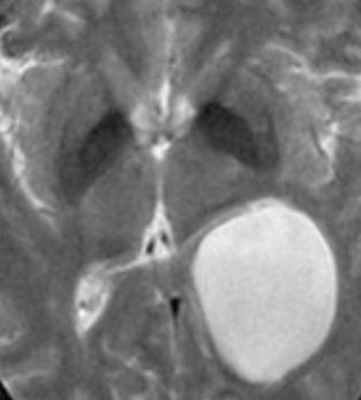

о Киста локализуется вдоль медиальных отделов височной доли, кзади и медиально по отношению к височному рогу, имеет ликворную плотность

• МРТ:

о Сигнал схож с сигналом от СМЖ на всех последовательностях:

- FLAIR: полное подавление сигнала

- ДВИ: нет ограничения диффузии

- Постконтрастные Т1-ВИ: контрастное усиление отсутствует

о Сагиттальные томограммы: типичная веретеновидная форма